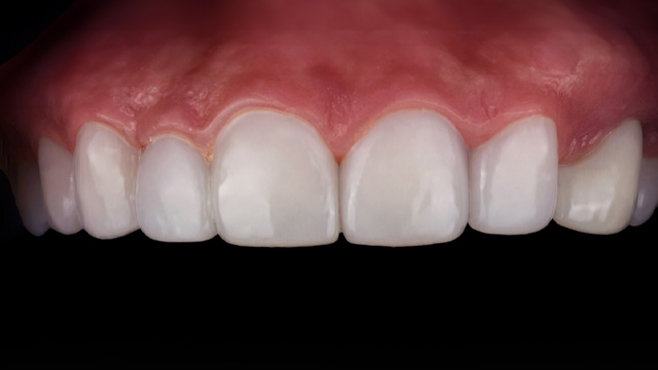

맞는 건 괜찮은데… 충치는 못 참겠습니다|20대 격투기 선수 치과 방문기

2026.02.06